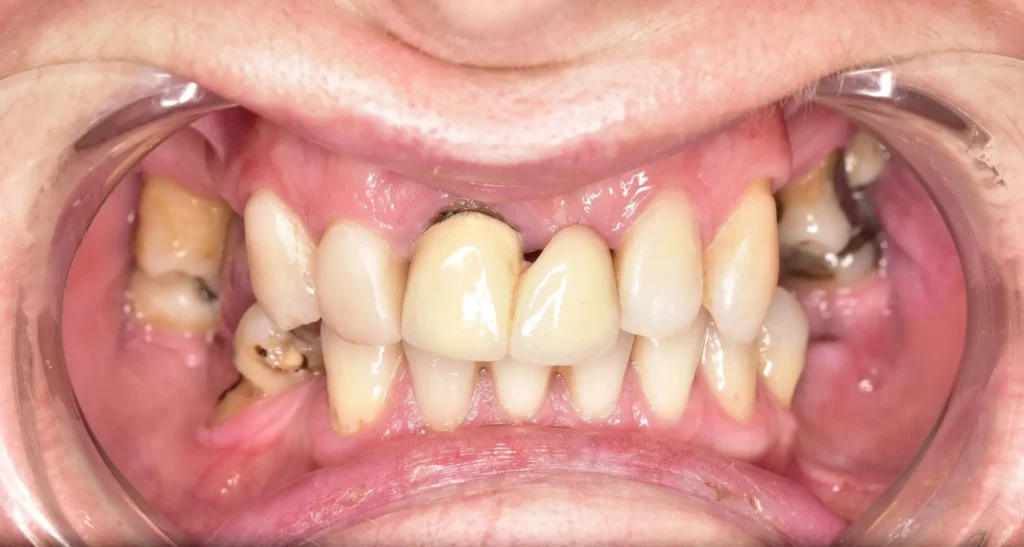

Pacjentka zgłosiła się do naszej kliniki z licznymi brakami w uzębieniu, które nie tylko wpływały na estetykę jej uśmiechu, ale także utrudniały codzienne funkcjonowanie. Nieprawidłowości w rozkładzie sił żucia, trudności w artykulacji oraz dyskomfort psychiczny związany z niepełnym uzębieniem stanowiły istotny problem, wymagający interdyscyplinarnego podejścia terapeutycznego.

Proces leczenia rozpoczęliśmy od kompleksowej diagnostyki oraz wdrożenia leczenia zachowawczego, którego celem było przygotowanie zębów do dalszej odbudowy protetycznej. W przypadku zębów niemożliwych do uratowania podjęliśmy decyzję o ich ekstrakcji, co pozwoliło na eliminację potencjalnych źródeł stanu zapalnego i przywrócenie prawidłowych warunków okluzyjnych.

Kluczowym etapem terapii była rekonstrukcja braków zębowych z wykorzystaniem mostów protetycznych. W odcinku przednim zastosowaliśmy estetyczne mosty pełnoceramiczne na podbudowie z tlenku cyrkonu, które dzięki swoim właściwościom optycznym doskonale imitują naturalną translucencję szkliwa i harmonijnie komponują się z fizjonomią twarzy pacjentki. W odcinkach bocznych, ze względu na większe obciążenia mechaniczne związane z żuciem, zdecydowaliśmy się na zastosowanie mostów na podbudowie metalowej, gwarantujących trwałość i wysoką odporność na siły działające w odcinku bocznym.

Efekt leczenia to pełny, funkcjonalny i estetyczny uśmiech, który nie tylko przywrócił pacjentce komfort w codziennym funkcjonowaniu, ale również znacząco wpłynął na jej pewność siebie i jakość życia. Dzięki indywidualnie dopasowanemu planowi leczenia oraz zastosowaniu nowoczesnych technologii protetycznych udało się osiągnąć rezultat spełniający zarówno wymagania estetyczne, jak i biomechaniczne.